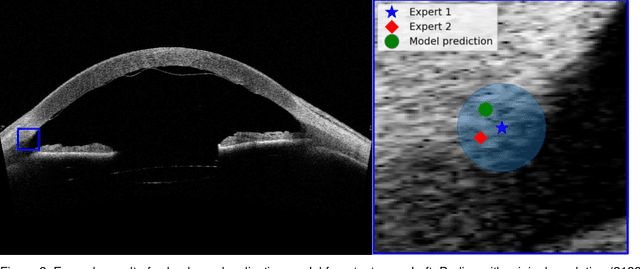

Abstract:Purpose: We developed a method to automatically locate and quantify graft detachment after Descemet's Membrane Endothelial Keratoplasty (DMEK) in Anterior Segment Optical Coherence Tomography (AS-OCT) scans. Methods: 1280 AS-OCT B-scans were annotated by a DMEK expert. Using the annotations, a deep learning pipeline was developed to localize scleral spur, center the AS-OCT B-scans and segment the detached graft sections. Detachment segmentation model performance was evaluated per B-scan by comparing (1) length of detachment and (2) horizontal projection of the detached sections with the expert annotations. Horizontal projections were used to construct graft detachment maps. All final evaluations were done on a test set that was set apart during training of the models. A second DMEK expert annotated the test set to determine inter-rater performance. Results: Mean scleral spur localization error was 0.155 mm, whereas the inter-rater difference was 0.090 mm. The estimated graft detachment lengths were in 69% of the cases within a 10-pixel (~150{\mu}m) difference from the ground truth (77% for the second DMEK expert). Dice scores for the horizontal projections of all B-scans with detachments were 0.896 and 0.880 for our model and the second DMEK expert respectively. Conclusion: Our deep learning model can be used to automatically and instantly localize graft detachment in AS-OCT B-scans. Horizontal detachment projections can be determined with the same accuracy as a human DMEK expert, allowing for the construction of accurate graft detachment maps. Translational Relevance: Automated localization and quantification of graft detachment can support DMEK research and standardize clinical decision making.